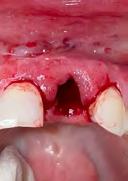

A healthy non-smoking 50-year-old female patient who desired a single-tooth solution to replace a non-restorable tooth, #12. A root fracture at the level of the palatal post was diagnosed in a root canaled tooth. Maintaining esthetics of the adjacent teeth was important as they are also restored with single full coverage porcelain crowns.

1. Pre-operative assessment demonstrates minimal zone and thickness of buccal keratinized gingiva, with a medium periodontal phenotype.

3. Minimally invasive removal of #12 using only a buccal approach mini-flap showing an intact buccal plate with immediate placement of the implant (1 mm below the intact buccal wall) in a screw-retained position. A 3mm buccal gap is measured and a 1.5mm palatal gap.